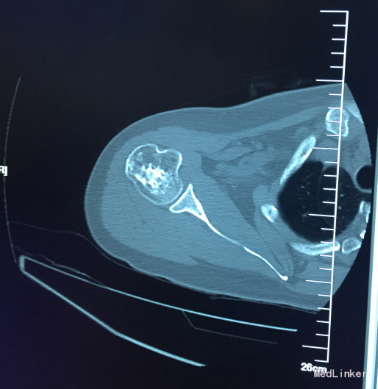

患者,中年女性,以“右肩疼痛伴活动障碍2年余”入院查体:约胸8椎体棘突及右侧胸背部压痛及叩痛阳性,不伴放射痛,颈椎及腰椎无明显压痛,脊柱活动度基本正常,肱骨近端压痛轻度阳性,右肩活动受限,外展95°,前屈95°,后伸15°。

右肩X片示:右肱骨近端髓腔片状高密度混杂影,行CT为右侧肱骨近端改变,考虑骨纤维异常增生症可能。

行臂丛麻醉下行右肱骨近端病灶刮除植骨术,将骨髓腔内病灶组织完全刮除.术后病理诊断为:骨纤维异常增生

诊断:右肱骨近端骨纤维异常增生症.讨论:术后给予消肿,止痛,胸背疼痛较前缓解,伤口愈合良好,局部无红肿硬节及渗出,出院后应将逐步适量功能锻炼;伤口定期换药,术后两周拆线,加强营养支持,补钙治疗,促进骨愈合。